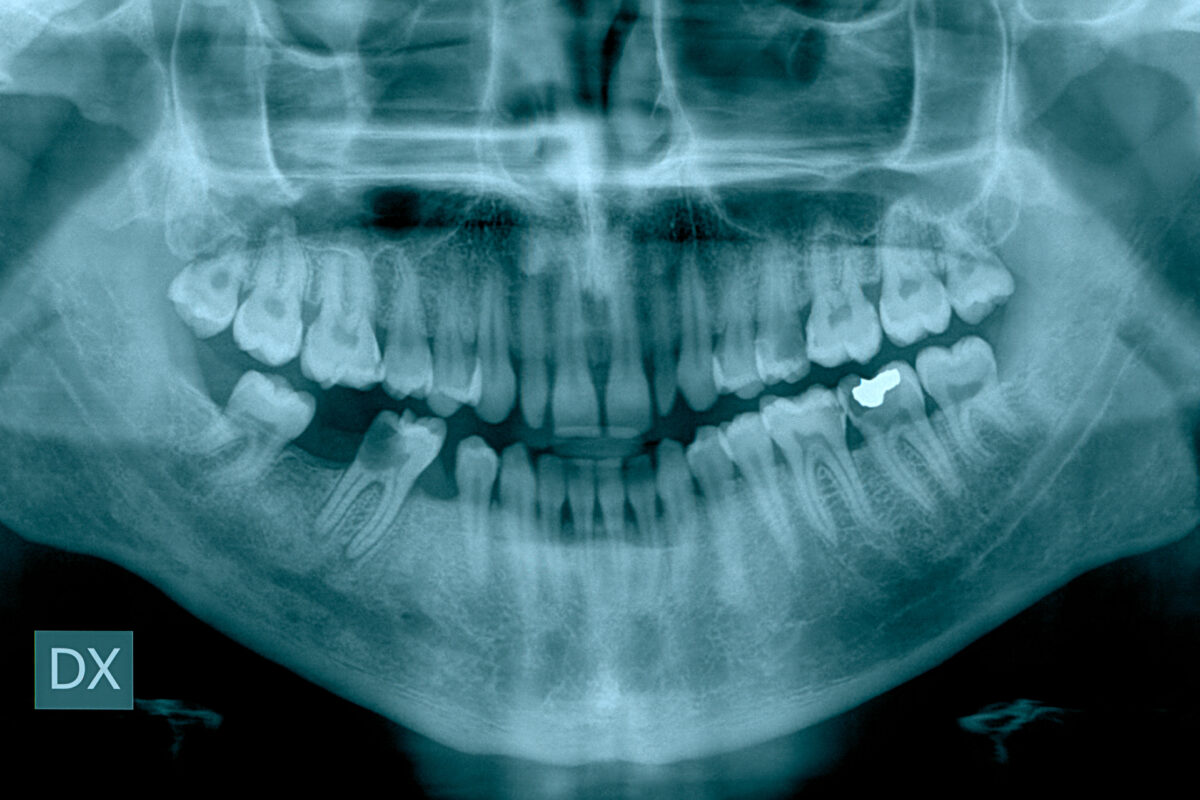

One of the strongest shields against gum disease is regular, preventive dental care. It is not just about cleaning, though that’s part of it. Preventive dental care focuses more on spotting trouble when it is still reversible. During a routine exam, your dentist checks your gums for signs of inflammation, recession, or deep pockets where bacteria might be lurking.

If your dentist notices the beginnings of gum disease, they will not just tell you to brush more. In most cases, you will get a personalised treatment plan aimed at protecting your oral health while also preserving your smile. Maybe that means visiting more frequently for deep cleans. Or maybe you will need a procedure called scaling and root planing, which clears bacteria from under the gums and smooths root surfaces to boost the healing process.